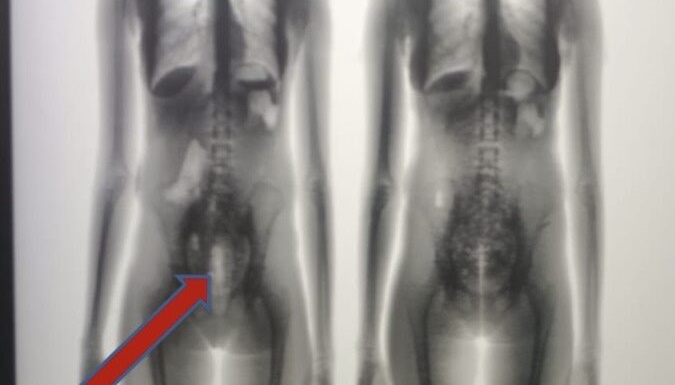

De acordo com informações da Polícia Penal, a suspeita pretendia visitar o marido, que está custodiado no Bloco 03 da unidade prisional. No entanto, ao passar pelo equipamento de escaneamento corporal (Body Scan), foi identificado um volume suspeito na região pélvica.